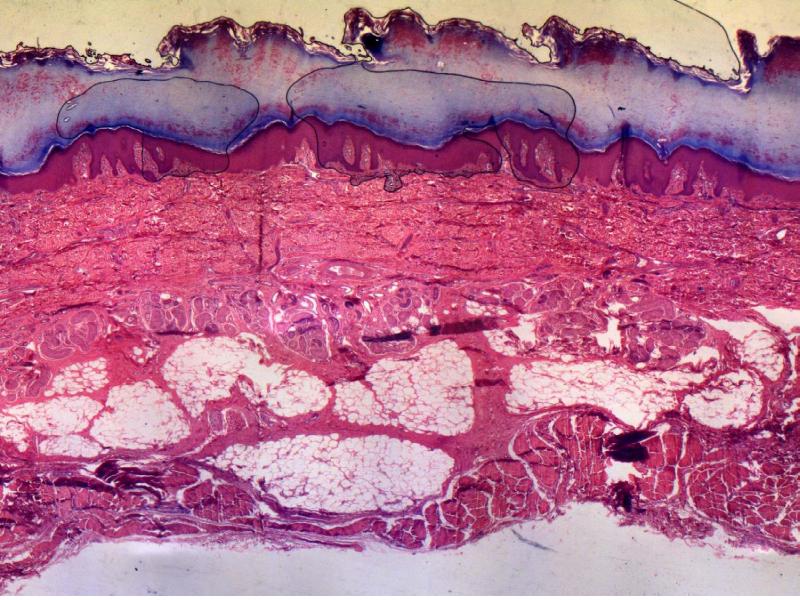

Slide 93: Thick skin - this slide is a section through the skin of the palm of the hand.

View the slides at low magnification. You should be able to see several layers, stained different colours and intensities. For a standard haematoxillin and eosin stained slide, there are three layers:

• A dark pink to red scalloped area - the epidermis.

• A central light pink eosinophilic area - the dermis.

• A very thick light pink area - the hypodermis.

• Look at the palm of your hand and fingertips. The thickened outer layer is the outer layer of stratified squamous keratinized epithelium.